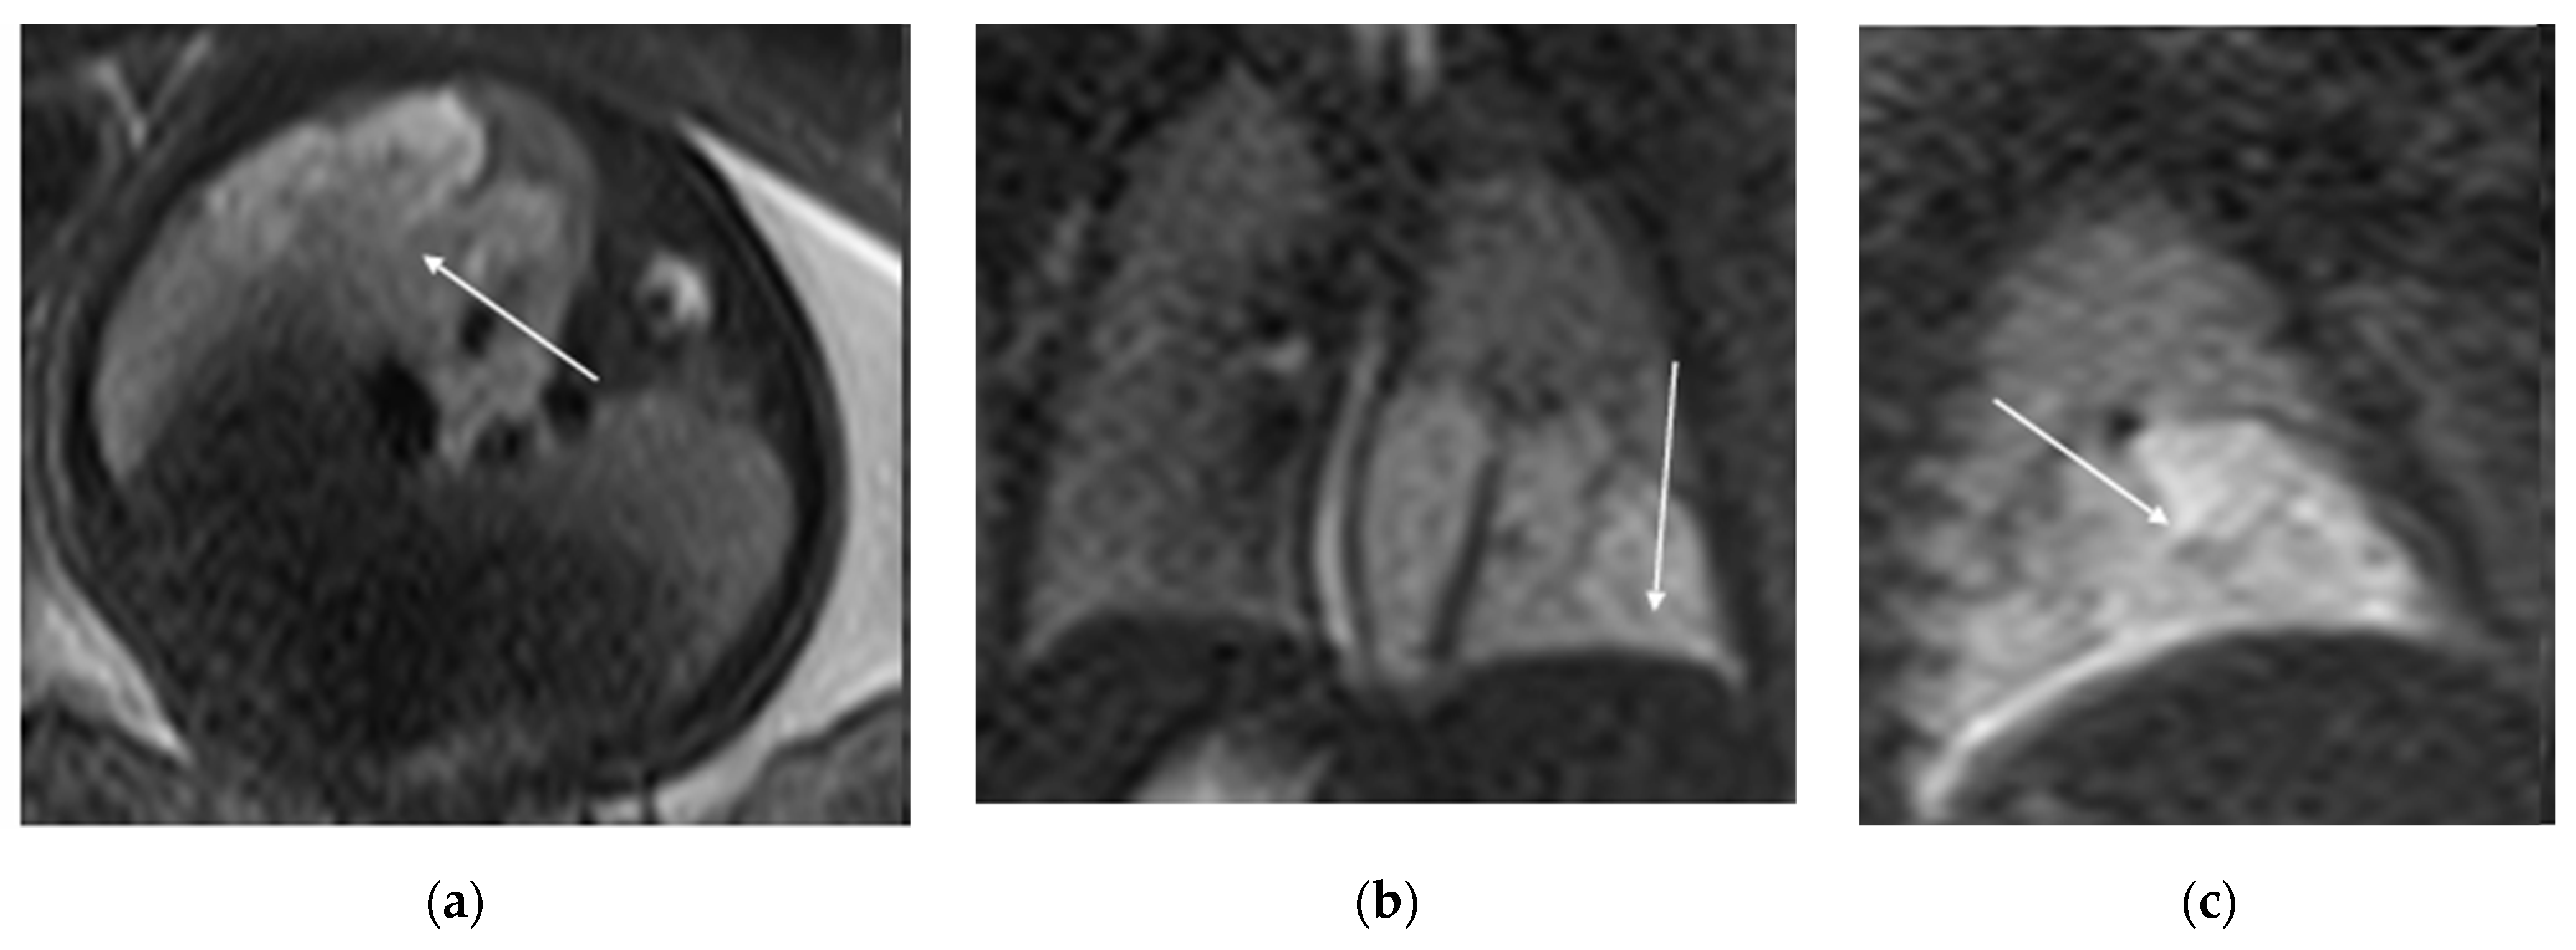

In prenatal diagnosis, MRI is valuable for better delineating and locating the mass. It also helps in assessing the contralateral lung. Key diagnostic signs on MRI include higher signal intensity than normal lung tissue, lower signal intensity than amniotic fluid, and the visible supply artery arising from the aorta (Figure 7) [8,11].

Figure 7. BPS at 27 weeks gestation. The coronal image shows a mass with higher signal intensity than the normal lung but lower signal intensity than amniotic fluid. The consolidation shifts the heart to the right (black arrow). There is a feeding artery from the aorta to suggest the diagnosis of sequestration (blue arrow).